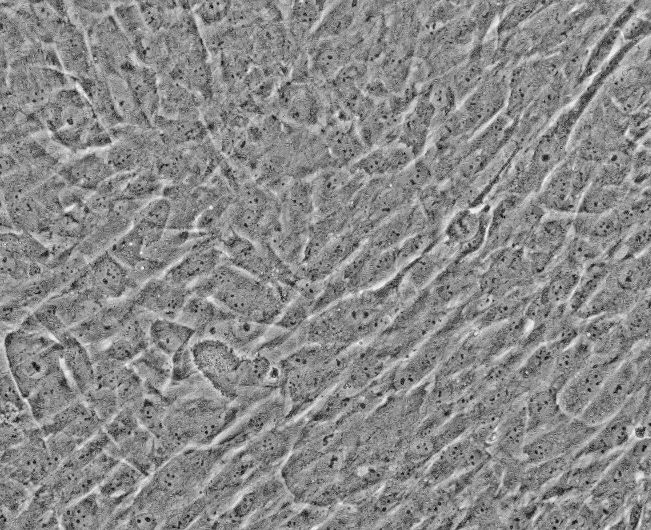

来自ScienCell研究实验室的HUVSMC从人脐静脉中分离出来。HUVSMC在*代冷冻保存并冷冻。每个小瓶含有>5×10^5个细胞,1ml体积。HUVSMC的特征在于用对α-平滑肌肌动蛋白和结蛋白特异的抗体的免疫荧光。HUVSMC对HIV-1,HBV,HCV,支原体,细菌,酵母和真菌均为阴性。在ScienCell研究实验室提供的条件下,HUVSMC保证进一步扩大15次群体倍增。

血管平滑肌细胞(SMC)是动脉疾病发展的主要原因[1]。血管SMC转变为增殖表型的能力是血管疾病发展和进展的主要因素之一。血管平滑肌细胞表达ICAM-1和VCAM-1,这可能有助于血管壁的炎症反应,并可能积极参与血管疾病的进展[2]。培养中的血管SMC在血管疾病研究中起重要作用,可用于鉴定治疗动脉疾病的新治疗靶点。